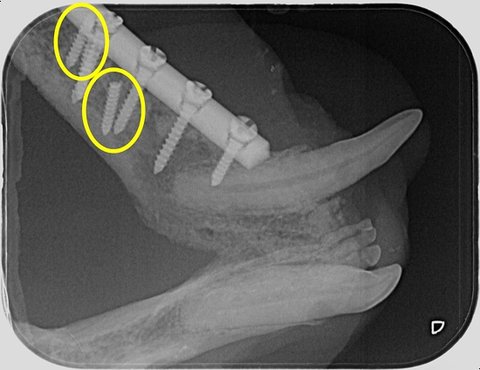

2년 전 구조 당시 구강 종양으로 아랫턱뼈를 잘라내고 플레이트로 고정을 했는데 나사가 풀려 재수술을 세 번이나 했어요.

마지막 수술이 지난 10월 29일이었는데 그 때는 다시 뼈를 붙여서 플레이트를 박았어요.

다른 전문 병원 가서 ct를 찍어보니 뼈는 다시 벌어져 있고

나사 여러개가 뼈에 박혀 있었어요.